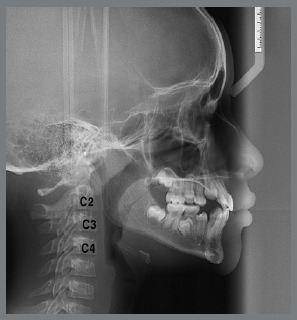

Material and methods: A total of 148 lateral cephalograms (78 males, 70 females) of Class II malocclusion patients, and 60 lateral cephalograms (30 males, 30 females) of normal occlusion patients were included. The following linear cephalometric measurements were performed: Co-Gn (effective mandibular length), Co-Go (ramus height), and Go-Gn (length of mandibular body). Mean values of increments between stages (I-A, A-T, I-T) were obtained for each group and gender. Results were compared using the Student t-test, and a significance level of 0.05% was adopted.

Abstract Image